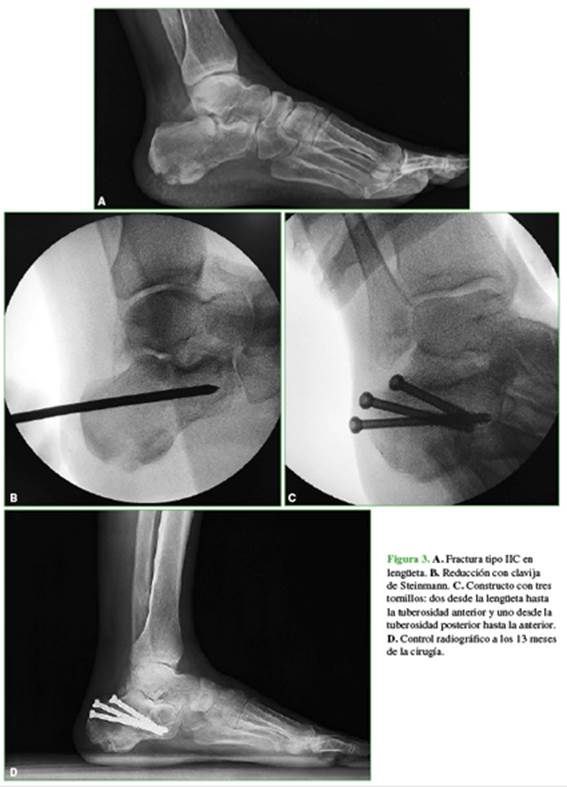

Si la reducción de los ángulos de Böhler y de Gissane es buena, se procede a la estabilización con tornillos. Utilizamos diferentes opciones: 3,5 mm corticales; 4,0 mm esponjosa canulados; 6,5 mm esponjosa canulados y 5 mm bloqueados. El constructo depende del tamaño de los fragmentos y del patrón de la fractura evaluados antes de la reconstrucción 3D. En algunos casos, colocamos tornillos que fijen la lengüeta desde el nivel superoexterno y superomedial hasta la tuberosidad anterior, la tuberosidad posterior a la anterior (Figura 3) o desde la tuberosidad posterior hasta el fragmento en lengüeta (Figura 4).

Los abordajes quirúrgicos siguen generando controversia, aunque se ha demostrado que las técnicas mininvasivas disminuyen las complicaciones de partes blandas y las infecciones comparadas con el abordaje lateral extendido.6 Ha surgido una amplia variedad de técnicas percutáneas para disminuir los problemas de partes blandas.6,15 No hay consenso sobre qué tipos de fracturas deben ser tratadas por vía percutánea. Algunos autores indican este procedimiento para fracturas tipos II, III y IV de Sanders,16,17 mientras otros solo para el tipo IIA, B y C con asistencia artroscópica para controlar la reducción articular, salvo en las tipo IIC donde la carilla articular está desplazada,

pero intacta.18